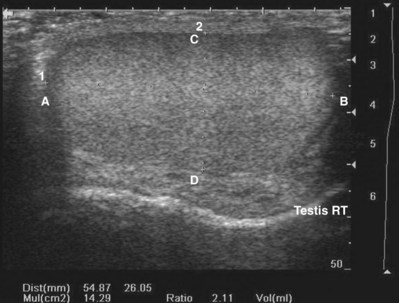

By convention, structures imaged by ultrasonography should be oriented so that the superior aspect of the structure is to the left as the image is viewed and the inferior aspect of the structure to the right. With paired structures it is critically important to document right or left. It is useful to use equipment-generated icons to illustrate patient position and the orientation of insonation (Fig. 4–30).

Figure 4–30 In this sagittal image of the right testis, the superior pole of the testis (A) is to the left, the inferior pole of the testis (B) is to the right. The anterior aspect of the testis (C) is at the top of the image and the posterior aspect (D) at the bottom. Without the label, there would be no way to distinguish the right from the left testis.